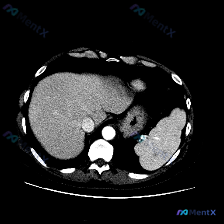

这次的情况有点特别:临床提示关注“脾脏病变”,但提供的是一张单张的腹部CT横断面软组织窗图像。

先说说图像里能看到的:

- 肝脏:实质密度均匀,无局灶性占位,边缘光滑,肝叶比例正常;

- 脾脏:位于左侧,形态、大小在本断面观上无增大,实质密度均匀,未见明确的局灶性低或高密度异常;

- 血管:腹主动脉显影良好,管壁光滑,管径正常;下腔静脉横断面形态良好,无明显血栓征象;

- 其他:腹腔内无游离积液,脂肪间隙清晰,可见的胃壁厚度均匀,无异常增厚。